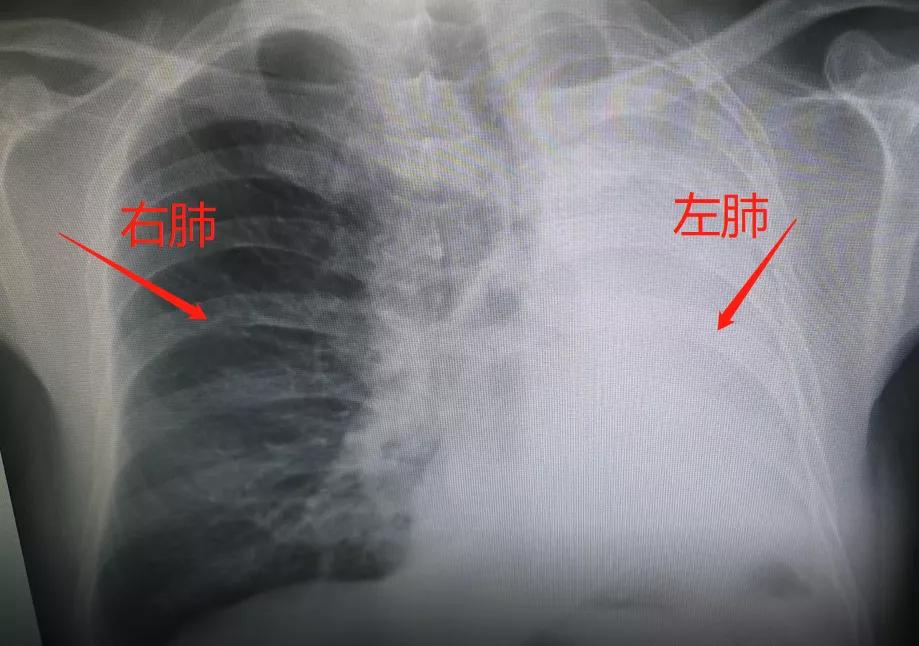

万大爷今年52岁 , 是个老烟民 , 吸烟30多年 。 因为咳嗽七个多月(他的心到底有多大)到医院去检查 , 拍片子发现左肺居然没了!

患者的CT图 , 图中正常的右肺充满了空气 。 而左肺可以从纵膈窗看到 , 已经成实变不张 , 并且有一些积液的表现 。 在支气管镜继续往下延伸——像地铁进了隧道一样——的时候 , 我们发现了左边有一个肿瘤 , 堵死了左主支气管远端的开口处 。 正是因为肿瘤堵死在这里 , 导致空气不能够进入左侧的肺组织 , 引起了整个左肺的萎陷、不张和实变 。